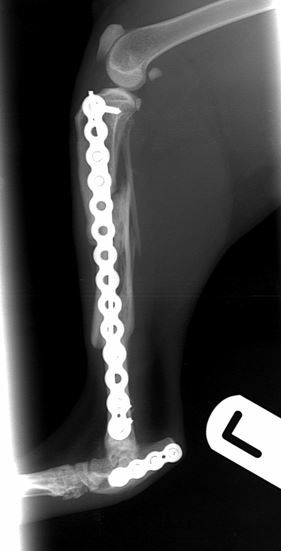

radiographic union of both fractures        radiographic union of both fractures

Fig. 4. At 10-weeks there is radiographic union of both fractures

The cat was weight bearing the day after surgery and has gone on to have an uneventful recovery